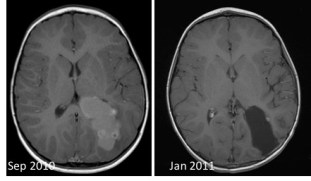

c’est un moyen efficace de prévenir les récidives, et même de faire disparaître un reliquat tumoral postopératoire non extirpable (ci-contre) ; elle est cependant grevée de morbidité en raison de sa neurotoxicité chez les jeunes enfants et du risque de tumeur radio-induite.